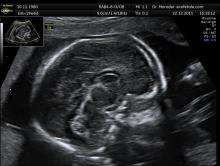

Inspection of the posterior fossa is a common feature of prenatal ultrasound and is used primarily to determine whether excess fluid or malformations of the cerebellum exist.[6] Anomalies of the cerebellar vermis are diagnosed in this manner and include phenotypes consistent with Dandy-Walker malformation, rhombencephalosynapsis, displaying no vermis with fusion of the cerebellar hemispheres, pontocerebellar hypoplasia, or stunted growth of the cerebellum, and neoplasms. In neonates, hypoxic injury to the cerebellum is fairly common, resulting in neuronal loss and gliosis. Symptoms of these disorders range from mild loss of fine motor control to severe mental retardation and death. Karyotyping has shown that most pathologies associated with the vermis are inherited though an autosomal recessive pattern, with most known mutations occurring on the X chromosome.[1][7]